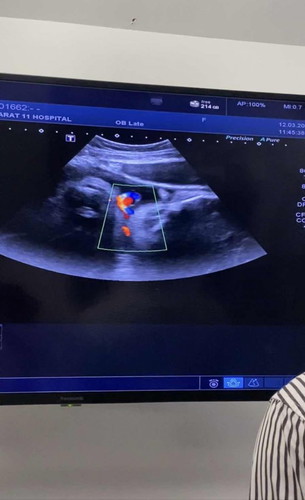

สายสะดือพันคอ 34+6W

แม่ๆบ้านไหนเคยผ่านประสบการณ์ สายสะดือพันคอลูกบ้างค่ะ รบกวนแชร์ประสบการณ์หน่อยค่ะ ตอนนี้กังวลมาก คุณหมอบอกว่าพัน 1 รอบเบาๆ 34+6W ค่ะ

เหมือนบ้านนี้เลยค่ะ รกพันคอ1รอบหลวมๆ แต่คุณหมอให้เฝ้าระวังนับลูกดิ้นค่ะ อีกอย่างบ้านนี้ผ่าคลอดหมอเลยบอกไม่น่ากังวลเท่าไหร่คะ